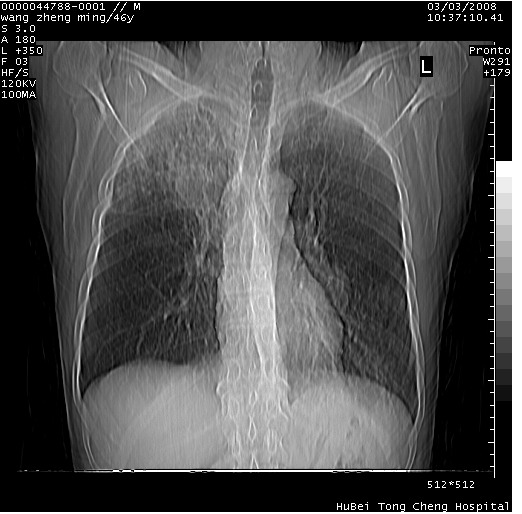

以下是引用卜一在2008-3-22 1:37:00的发言:[br]右肺实质性肿块,边缘不整,明显见毛刺征 分叶征及胸膜凹陷征,右上叶支气管明显变窄,远端散在的片状 斑片状实变影。另:左肺门较大肿块,支气管受累 变窄,远侧见阻塞性肺炎。纵隔内见肿大淋巴结。多考虑:右肺周围性肺癌伴左肺门 纵隔淋巴结转移!